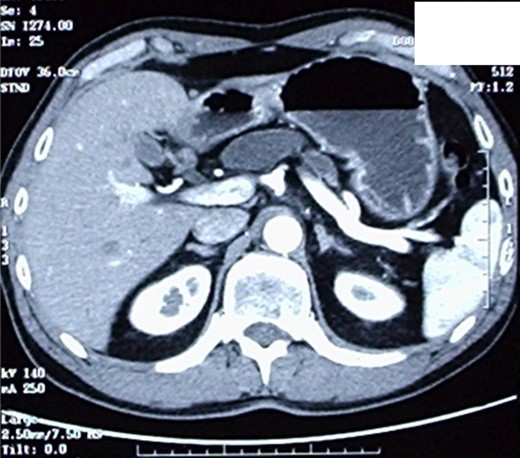

The patient therefore underwent a computed tomography (CT) scan (Figs 1 and 2) that revealed ‘a thickened duodenal wall and a sero-cystic lesion of the pancreatic head without contrast-enhancement, which compressed the duodenal lumen and caused a dilation of the Wirsung duct’. The liver, the gallbladder and the extrahepatic biliary tree were normal. No lymphadenopathy was found.

CT-scan, showing a sero-cystic lesion of the pancreatic head without contrast-enhancement, compressing the duodenal lumen and causing a dilation of the Wirsung duct.